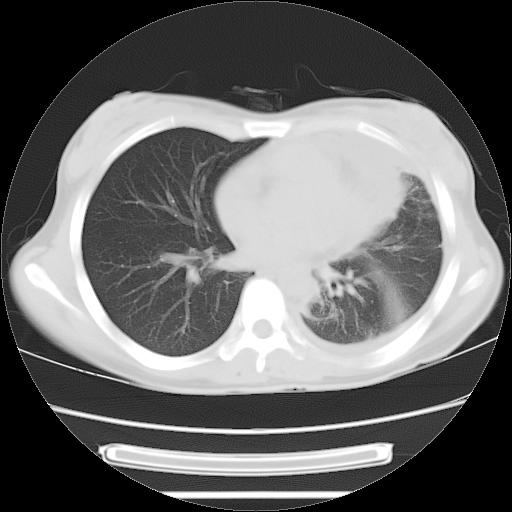

标题: CT21561:外院胸片提示胸腔积液,行CT检查。 [打印本页]

女,29岁,胸部不适,在外院胸片提示胸腔积液,到我院ct检查。

肺窗:

1、左侧包裹性积液伴叶间积液 2、右肺多发结节考虑增殖结节

左侧纵隔胸膜包裹性积液、左侧胸腔积液、胸膜肥厚粘莲,考虑结核性胸膜炎

左肺上叶不张,左侧胸水,叶间裂积液,纵隔淋巴结,脾脏钙化,考虑左肺上叶支气管内膜结核,结核性胸膜炎,脾结核

考虑:1.两肺tb;2.左侧胸膜炎、胸腔积液。

考虑两肺结核,左侧包裹性积液,叶间积液。

支持两肺继发性肺结核,左侧胸膜腔包裹性积液、胸膜肥厚,脾内多发钙化(结核钙化)。

右肺多发结节。左胸腔多发包裹性积液。